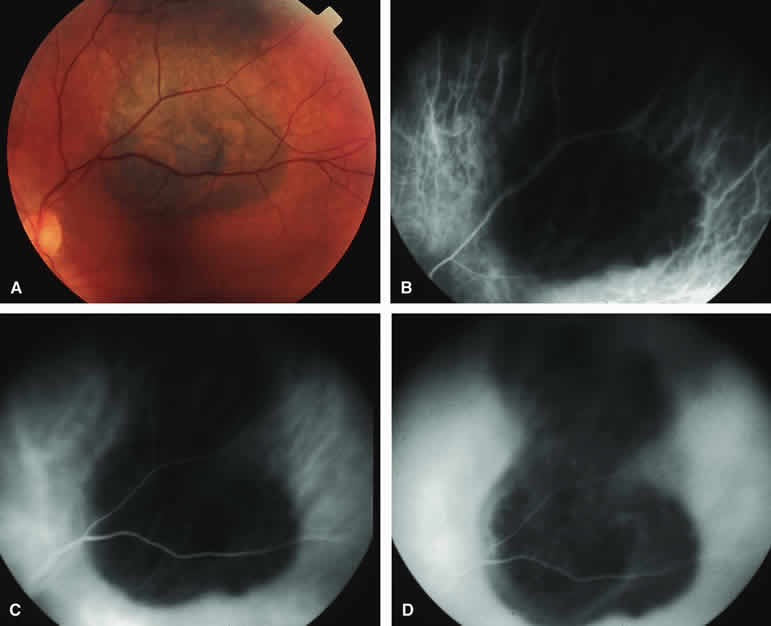

ICG angiography of a typical melanotic choroidal nevus (see Fig. 2) shows better definition of the basal area of the lesion than does fluorescein angiography. The entire lesion appears completely and uniformly dark throughout the ICG angiogram. Only the larger retinal blood vessels overlying the nevus are usually demonstrated on ICG angiography.